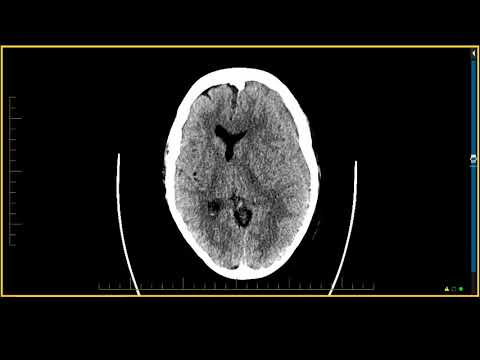

Midline brain shift may be evident in neuroimaging such as CT scanning. The sign is considered ominous because it is commonly associated with a distortion of the brain stem that can cause serious dysfunction evidenced by abnormal posturing and failure of the pupils to constrict in response to light.

Doctors detect midline shifts using a variety of methods. The most prominent measurement is done by a computed tomography (CT) scan and the CT Gold Standard is the standardized operating procedure for detecting MLS.

Since the midline shift is often easily visible with a CT scan, the high precision of Magnetic Resonance Imaging (MRI) is not necessary, but can be used with equally adequate results.

The brain is naturally balanced between the left and the right hemispheres. On a computed tomography (CT) scan that looks down at the brain from the top of the head, there is a groove that runs between both sides of the brain that is midline to the body.

The spinal cord emerges at the middle base of the brain and continues down the center of the back. A midline shift occurs when something pushes this natural centerline of the brain to the right or to the left. It is a concerning sign after head trauma.